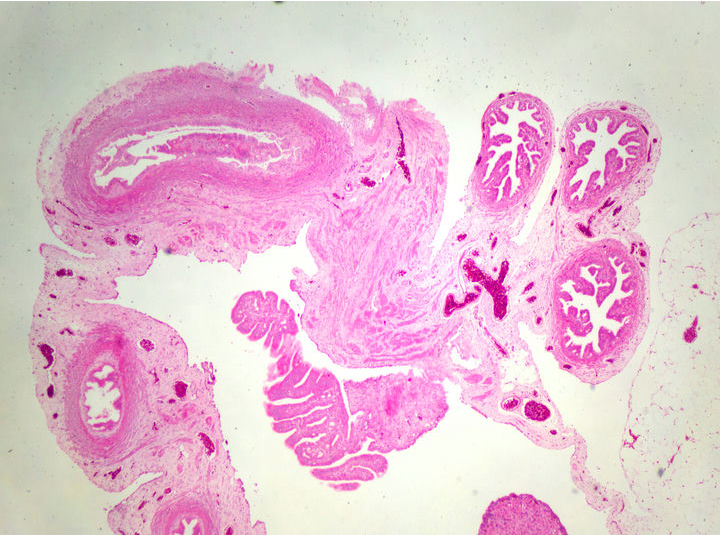

病理切片是病理科醫(yī)生確診病癥的重要工具,觀察病理切片一般使用生物顯微鏡明場(chǎng)觀察,一款好的病理切片顯微鏡,不僅要求使用舒適,還要成像清晰。在生物顯微鏡ML31的觀察下,經(jīng)過HE染色的卵巢切片呈粉紅色,并呈現(xiàn)出豐富而復(fù)雜的細(xì)節(jié)。

卵巢,作為女性生殖系統(tǒng)的重要器官,負(fù)責(zé)產(chǎn)生卵子和分泌性激素。透過生物顯微鏡ML31,我們可以看到許多不同種類的細(xì)胞。其中較突出的是卵原細(xì)胞,這是卵巢中產(chǎn)生卵子的母細(xì)胞。在染色切片中,卵原細(xì)胞呈現(xiàn)出較大的體積和較深的染色,與其他細(xì)胞有所區(qū)別。

通過生物顯微鏡ML31觀察卵巢染色切片,我們可以了解卵巢的基本結(jié)構(gòu)和功能。這不僅有助于我們對(duì)生殖系統(tǒng)的理解,也為研究卵巢疾病的病因、病理和治療方法提供了重要依據(jù)。

明美生物顯微鏡ML31是一款無限遠(yuǎn)獨(dú)立消色差的正置顯微鏡,采用大視野高眼點(diǎn)目鏡、平場(chǎng)消色差物鏡、長(zhǎng)壽命LED科勒照明等設(shè)計(jì),具有豐富的擴(kuò)展?jié)摿Γm合病理觀察、生物切片觀察、細(xì)菌觀察、中藥鑒定等應(yīng)用。